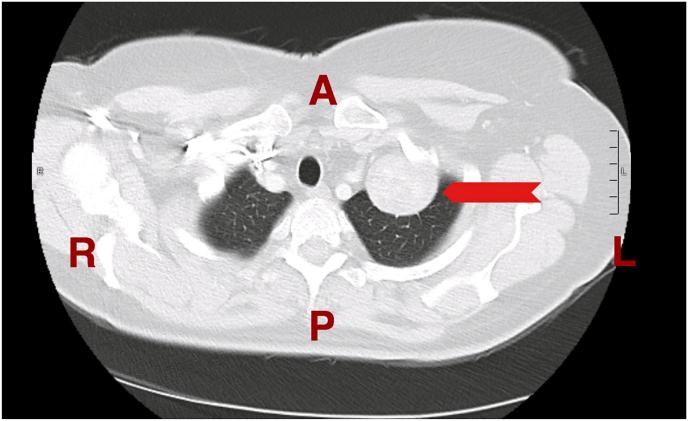

Solitary fibrous tumors of the pleura (SFTPs) are rare neoplasms of mesenchymal origin most commonly arising in the pleura and have a benign biological behavior in the majority of cases. Most patients with SFTPs are asymptomatic; however, symptoms are mostly related to the mass effect within the thoracic cavity. Chest computed tomography (CT) scanning is the radiographic test of choice, but findings lack specificity. Surgical resection is the treatment of choice for most patients. Long-term survival after resection of benign SFTPs is excellent. In this case series, we present two females, one presented with shortness of breath (SOB) and nonproductive cough and the other one was referred because of abnormal x-ray findings. The histological as well as the immunohistochemical examination revealed the mass to be a solitary fibrous tumor of the pleura.

胸膜孤立性纤维瘤(SFTPs)是一种罕见的间叶源性肿瘤,最常起源于胸膜,大多数病例具有良性生物学行为。大多数SFTPs患者无症状;然而,症状大多与胸腔内的肿块效应有关。胸部计算机断层扫描(CT)是首选的影像学检查,但检查结果缺乏特异性。手术切除是大多数患者的首选治疗方法。良性SFTPs切除后的长期生存率很高。在本病例系列中,我们报告了两名女性,一名表现为呼吸急促(SOB)和干咳,另一名因X线检查结果异常而转诊。组织学及免疫组化检查显示该肿块为胸膜孤立性纤维瘤。